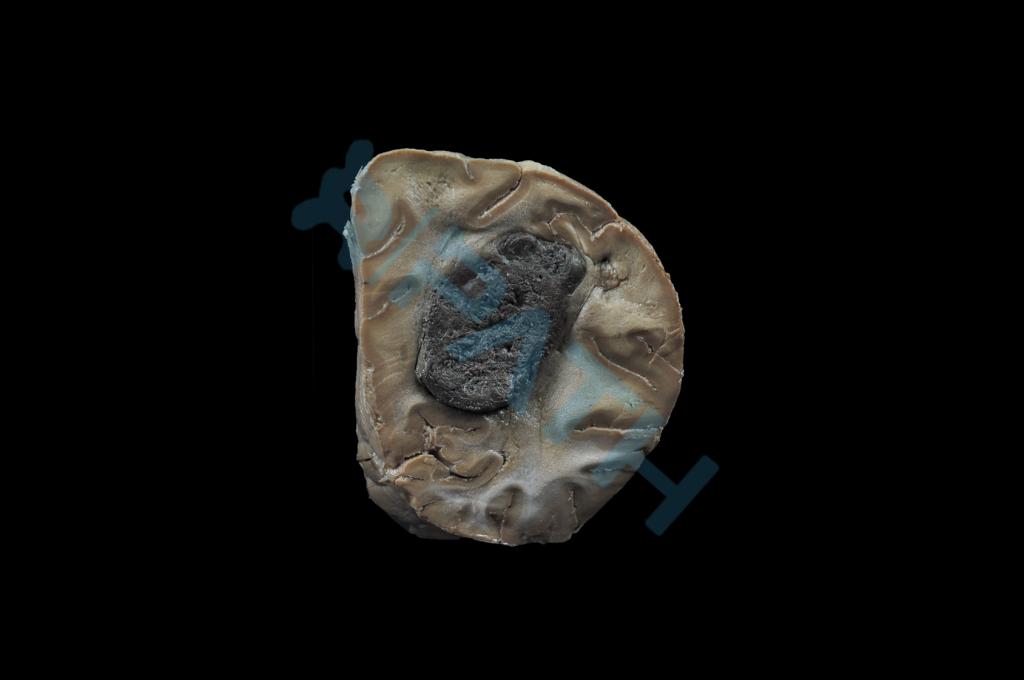

脑转移癌